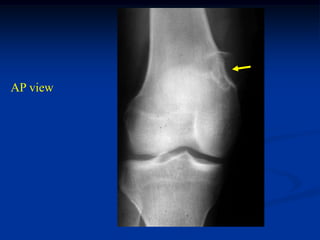

AP view